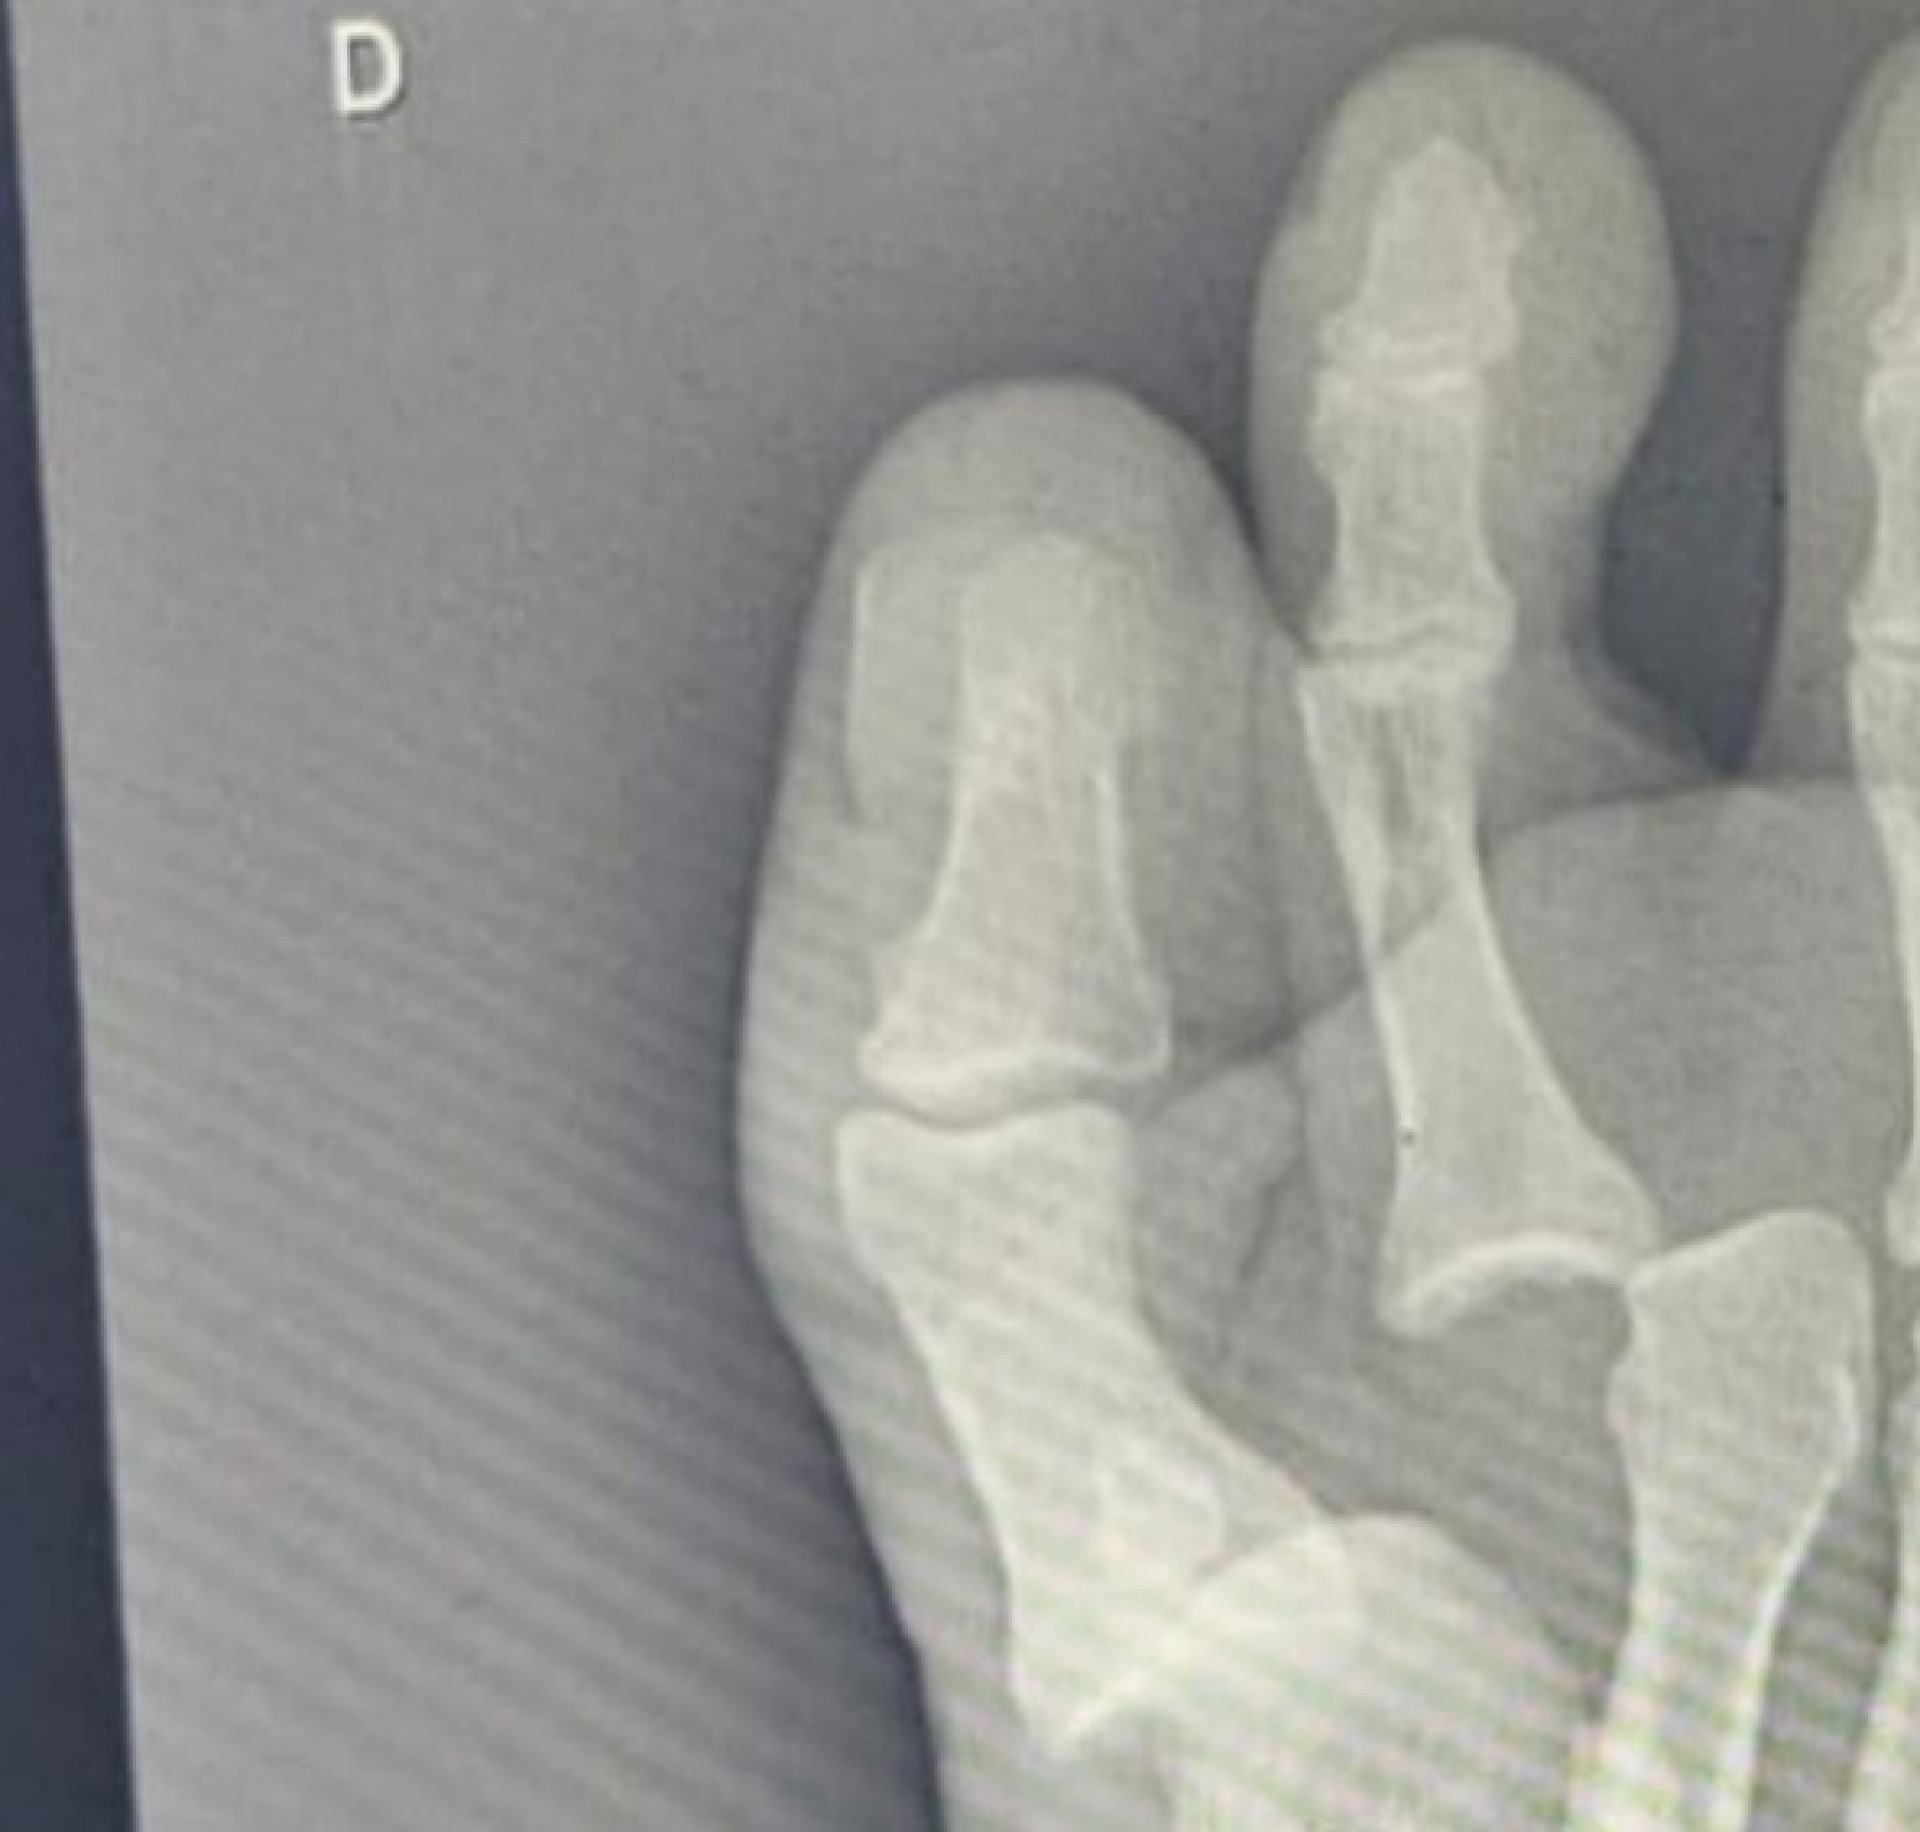

A deputada federal e ex-prefeita de Fortaleza, Luizianne Lins (PT) acabou se machucando quando participava de um evento de campanha do candidato petista em Caucaia, Waldemir Catanho. Segundo postagem dela própria nas redes sociais, a sandália que usava teve a sola descolada, o que acabou fazendo com que a parlamentar machucasse os dedos de um dos pés e fosse parar no hospital. "O pé foi e o calçado ficou! Corri para o Hospital Municipal de Caucaia, onde fiz o raio-X do pé, detectando que os ossinhos estavam bastante deslocados, 'confusos'", explicou a petista.

Luizianne conta que os dedos "mudaram de direção, desalinharam". Ela afirma que foi levada ao Hospital Municipal de Caucaia, onde foi diagnosticado que, apesar de não haver fraturas, ela precisaria ser submetida a um procedimento para recolocá-los no lugar, o que já foi feito com sucesso. "Ufa, pessoal. Envergou, mas não quebrou", brincou. A ex-prefeita da capital agradeceu aos funcionários que a atenderam.